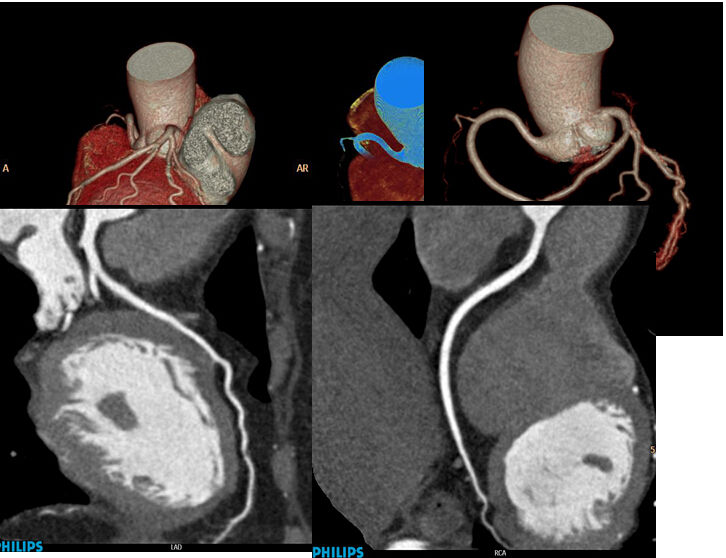

除開展全身(shēn)各部位常規檢查外,還先後開展了(le)全身(shēn)血管CTA成像、骨關(guān)節CT三維重建、磁共振擴散加權成像DWI、灌注成像PWI、磁敏感成像SWI、胰膽管水成像MRCP、泌尿系水成像MRU、内聽(tīng)道水成像、外周血管介入診療、消化(huà)道支架成形術、椎體(tǐ)成形術、椎間(jiān)盤消融術、經皮穿刺活檢術等新(xīn)技術。

冠狀動脈CTA